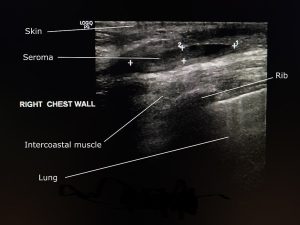

1. Identificar planos anatómicos

Piel → tejido subcutáneo → fascia → músculo

Hallazgos Típicos

Seroma simple:

• Anecoico

• Bordes definidos

• Sin señal Doppler interna

• Puede presentar septos finos